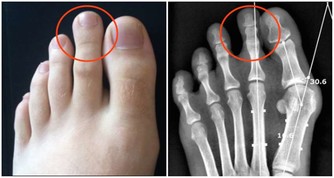

便秘也是誘發大腸癌的原因之一。

平時要養成良好的排便習慣,有便意就去排,不要忍著。預防便秘,平時多吃富含膳食纖維的食物,如番薯、花椰菜等。同時,多留意大便情況,出現血便應及時到醫院進行檢查,不要誤認為是痔瘡。